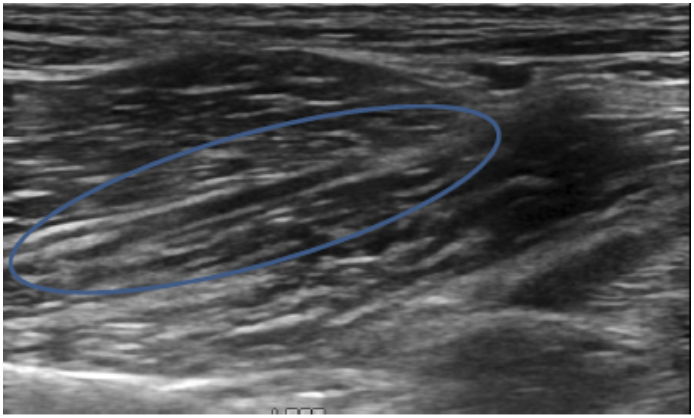

Clinical Evaluation of Iliopsoas Strain with Findings from Diagnostic Musculoskeletal Ultrasound in Agility Performance Canines – 73 Cases